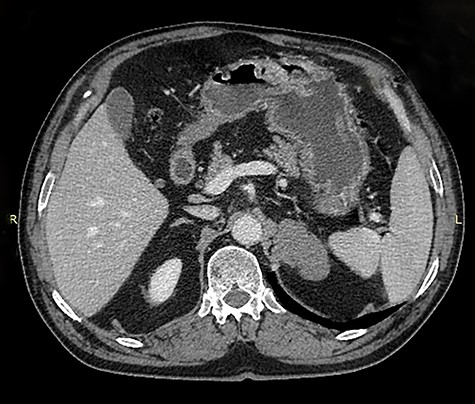

An asymptomatic 75-year-old Caucasian male was referred to our institution for the evaluation of an incidental left adrenal mass pointed out on computed tomography (CT) scan at medical checkup. The patient had a past medical history of hypertension and benign prostatic hyperplasia. The medication list included perindopril, indapamide, bisoprolol and tamsulosin. He had no previous surgeries and his family history was unremarkable. Physical examination was normal. Abdominal contrast-enhanced CT scan revealed a 5.6 × 3.5 × 3 cm, solid, nodular, hypodense mass that was thought to be arising from the left adrenal gland, suggesting an adenoma (Figs 1 and 2).

Axial image of contrast enhanced computed tomography of abdomen showing a mass that was thought to be arising from the left adrenal gland.